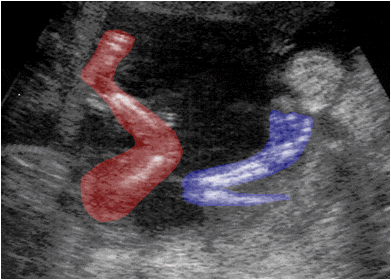

Ecografía fetal que muestra en un corte longitudinal la extremidad inferior (rojo) y la extremidad superior (azul).